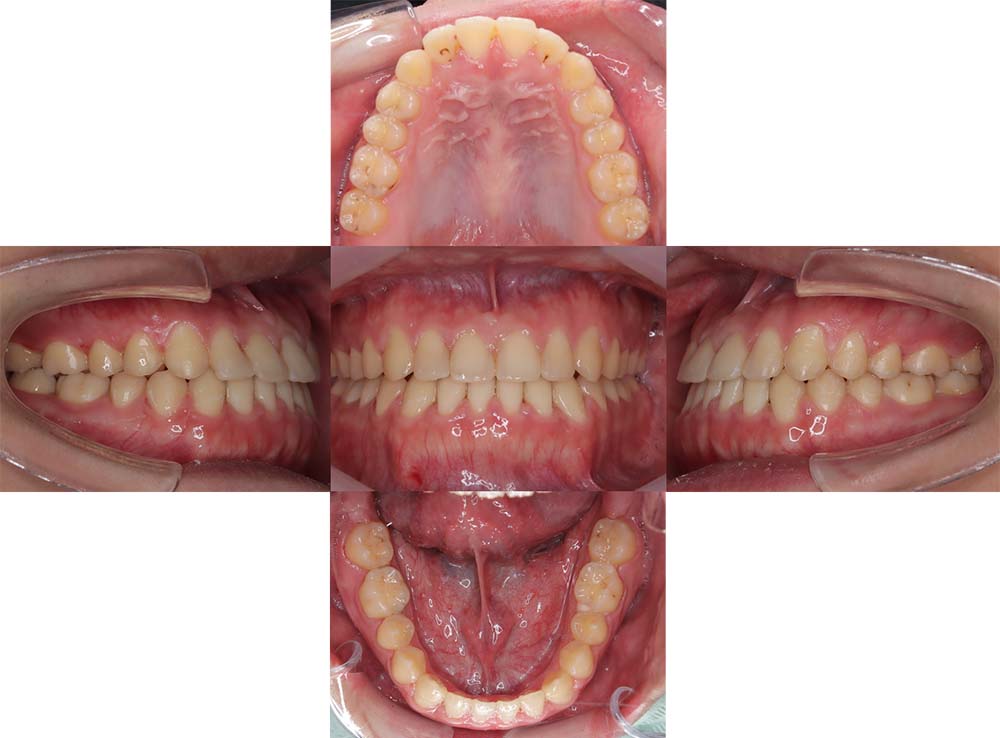

症例02

| 主訴 | 下あご顎が出ている。曲がっている。 |

| 診断名あるいは主な症状 | 反対咬合、非対称、空隙歯列、過蓋咬合 |

| 年齢/性別 | 19歳・女性 |

| 矯正ステージ | 大人の矯正治療 |

| 治療方法 | ワイヤー矯正、顎矯正手術の施行 |

| 抜歯部位/抜歯有無 | 非抜歯 |

| 治療内容 | 上下顎歯列を並べた後に顎矯正手術の施行。 |

| 費用 | 保険治療 |

| 治療期間 | 3年2ヶ月 |

| 主なリスク・副作用 | 痛み、歯根吸収、歯肉退縮、虫歯、後戻り |